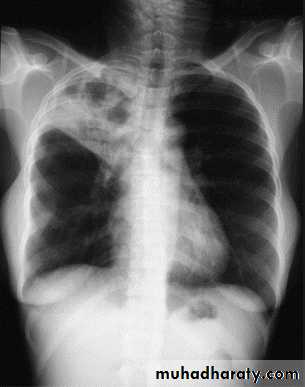

BRONCHOPNEUMONIA

Mycoplasma pneumonia. A 35 year old man presents with nonproductive cough and fever